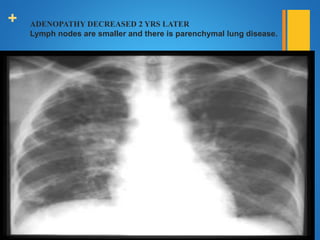

+ ADENOPATHY DECREASED 2 YRS LATER

Lymph nodes are smaller and there is parenchymal lung disease.